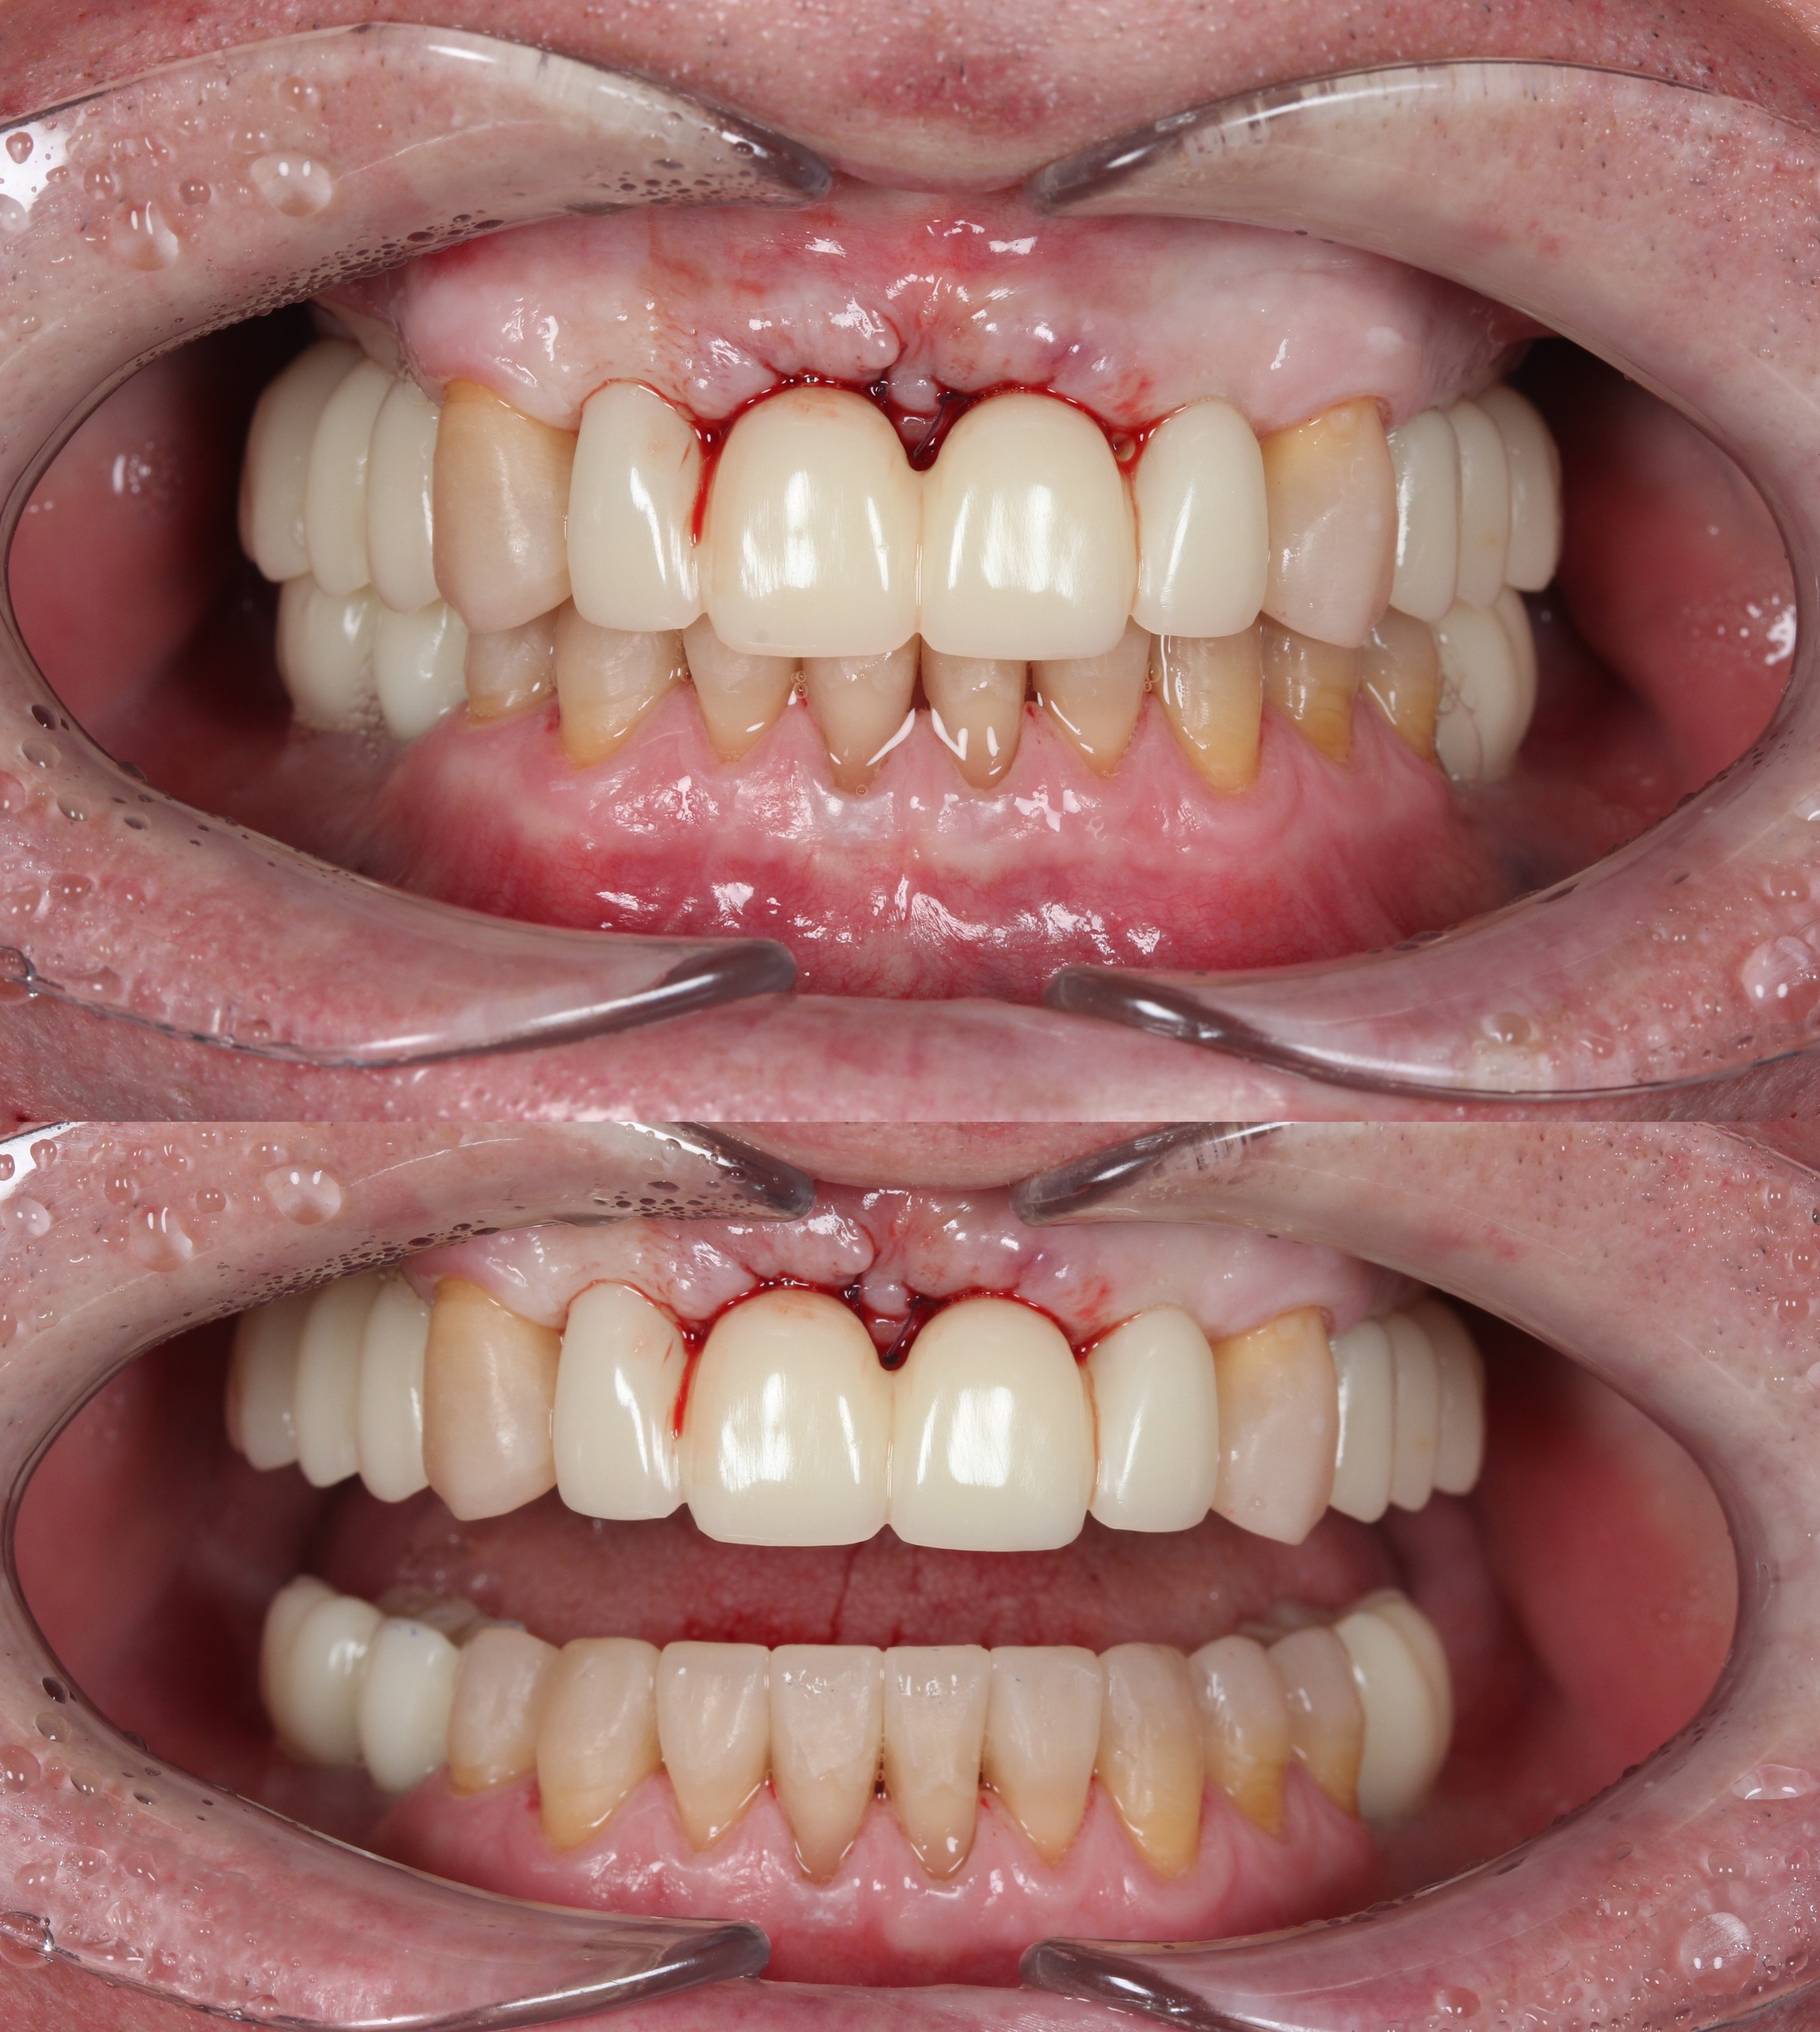

Спустя две недели произведена фиксация временных коронок.

Параллельно я удалил два центральных верхних резца, после чего были зафиксированы все остальные временные коронки.

Подчеркну - коронки временные (!), все они будут заменены на постоянные.

Вот так было:

А как стало на промежуточном этапе:

Согласитесь, выглядит очень даже неплохо, если опустить цвет.